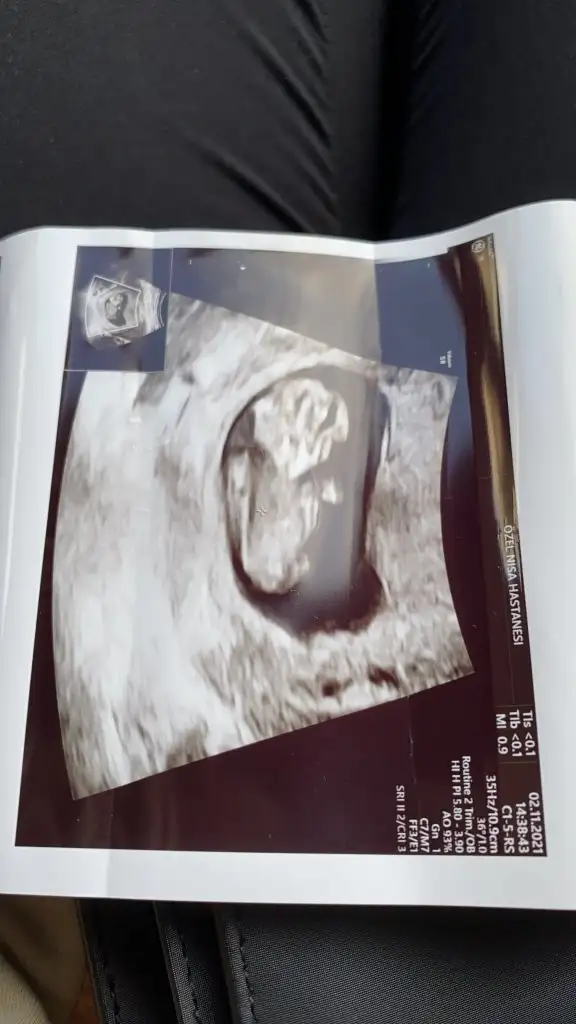

Ben kiza benzettim

Suan kac haftalik acaba? Tam belli olmuyor malesef

11Suan kac haftalik acaba? Tam belli olmuyor malesef